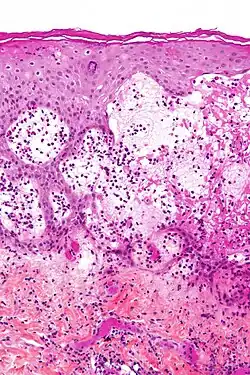

| Micrografia do penfigoide gestacional com as bolhas sub-epidérmicas características e eosinófilos abundantes. | |

Penfigóide gestacional é uma dermatose da gravidez. É uma doença autoimune e bolhosa da pele que ocorre durante a gravidez, geralmente no segundo ou terceiro trimestre e/ou imediatamente após o nascimento. Era inicialmente denominada herpes gestacional devido à aparência semelhante, embora não tenha nenhuma associação com o herpesvírus.[1][2][3]